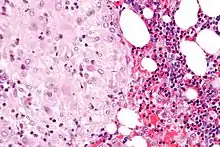

Micrograph of decidua in a lymph node. H&E stain.

Clinical significance

3. Wu, DC.; Hirschowitz, S.; Natarajan, S. (May 2005). "Ectopic decidua of pelvic lymph nodes: a potential diagnostic pitfall". Arch Pathol Lab Med. 129 (5): e117–20. doi:10.5858/2005-129-e117-EDOPLN. PMID 15859655.